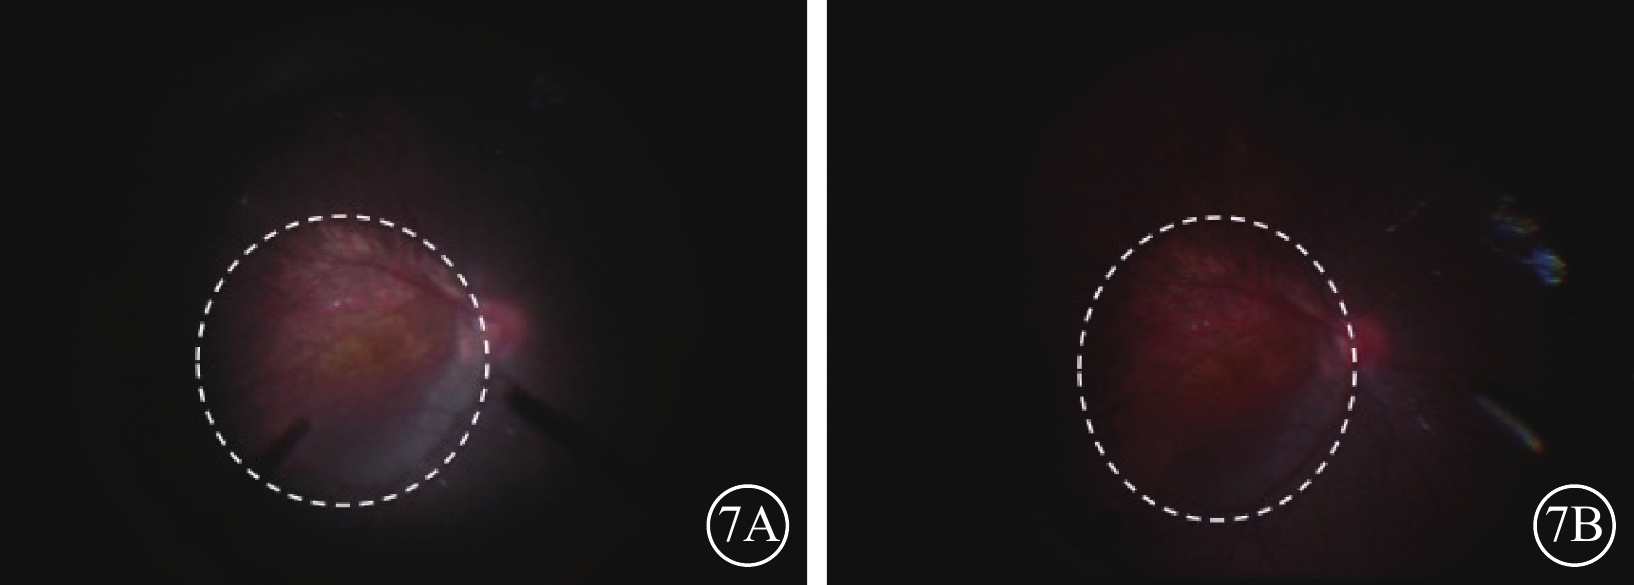

相對于對照組,手術者認為觀察組即3D數字化平視玻璃體視網膜手術技術下行兒童玻璃體視網膜手術有以下優勢:可在頸背部放松狀態下進行手術操作(圖1B),因此手術結束時疲勞感較輕。手術中圖像的分辨率和立體感較強,包括混濁晶狀體前囊膜皺褶(圖3)、后囊膜斑塊樣混濁(圖4)以及混濁后囊膜內的新生血管顯示更為清晰(圖5);PFV患兒受牽拉移位的睫狀突立體感更強(圖6),眼底圖像中黃斑區周圍的鞏膜葡萄腫更具立體感(圖7),因此具有更好的示范教學效果,眼前后節操作轉化時景深范圍較好。觀摩手術的其他眼科醫生及非眼科醫護人員均表達了3D數字化平視顯示屏相對于傳統光學顯微鏡下手術視頻顯示系統具有更好的畫面立體感和更高的分辨率,但第一助手醫生在3D數字化平視玻璃體視網膜技術下配合鞏膜外頂壓、剪線操作等顯微手術操作時需要歪頭側視45°~90°,長期操作引起頸部不適感。另外,患兒均在全身麻醉下進行手術,期間需要手術巡回護士和麻醉醫生進行必要的輸液管道、氣管插管檢查和確認以及全身生命體征指標的監測和調整等醫療行為,有一定比例的非眼科醫護人員表達了現有3D數字化平視顯示屏擺放位置妨礙了行使上述醫療行為的便捷性。